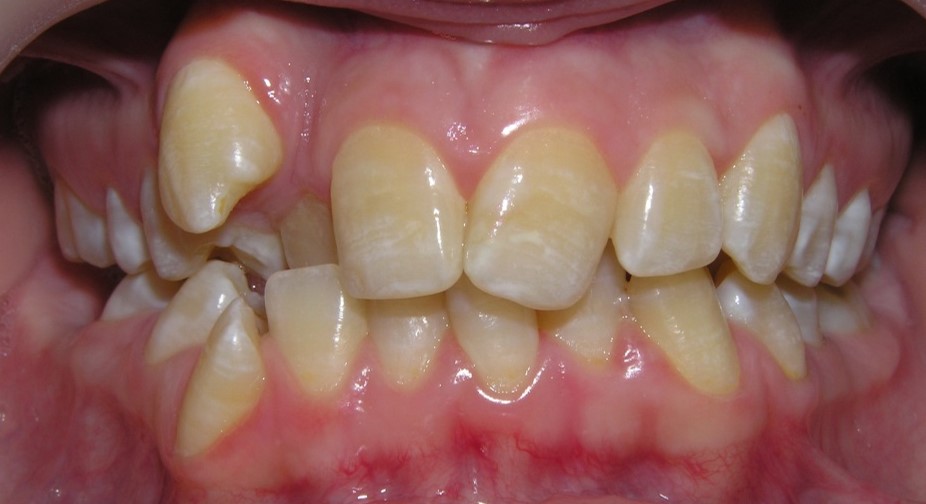

Pic.26. Crowding of the front teeth of the upper and lower jaws.